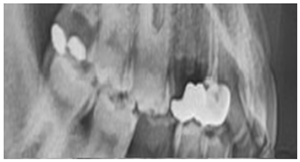

3.2. Dataset Description

3.3. Results Obtained from 2D Lateral Cephalogram Analysis Applying AI Techniques